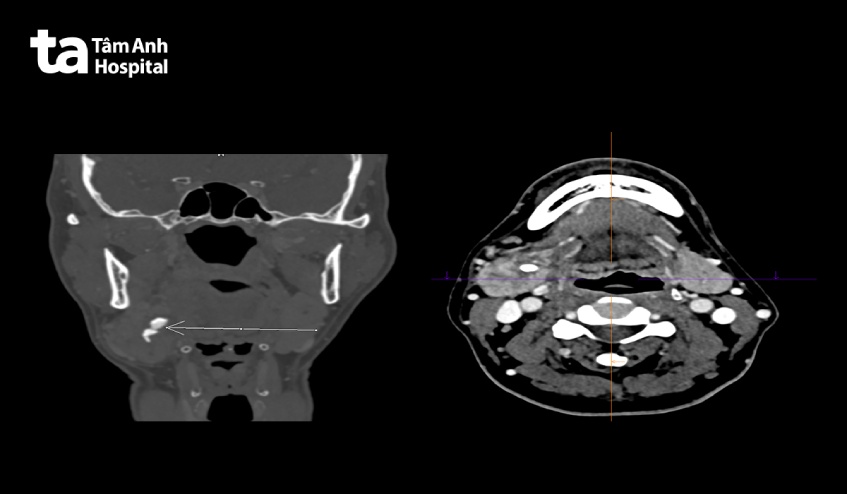

ThS.BS.CKI Phạm Thái Duy, Trung tâm Tai Mũi Họng Bệnh viện Đa khoa Tâm Anh TP.HCM cho biết, trước đó bệnh nhân đã thăm khám vài nơi đều được chẩn đoán là sỏi tuyến nước bọt dưới hàm phải. Bệnh nhân được chụp CT-scan để xác định lại chẩn đoán. Kết quả, sỏi nằm ở vùng tiếp giáp giữa tuyến và ống tuyến gây viêm phì đại tuyến và giãn rộng lòng ống. Tổng cộng có 3 viên sỏi, viên to nhất kích thước hơn 1,5cm; 2 viên còn lại kích thước khoảng 0,5-0,8cm. Đây là kích thước lớn, ít gặp nên cần phẫu thuật cắt tuyến mới lấy được sỏi.